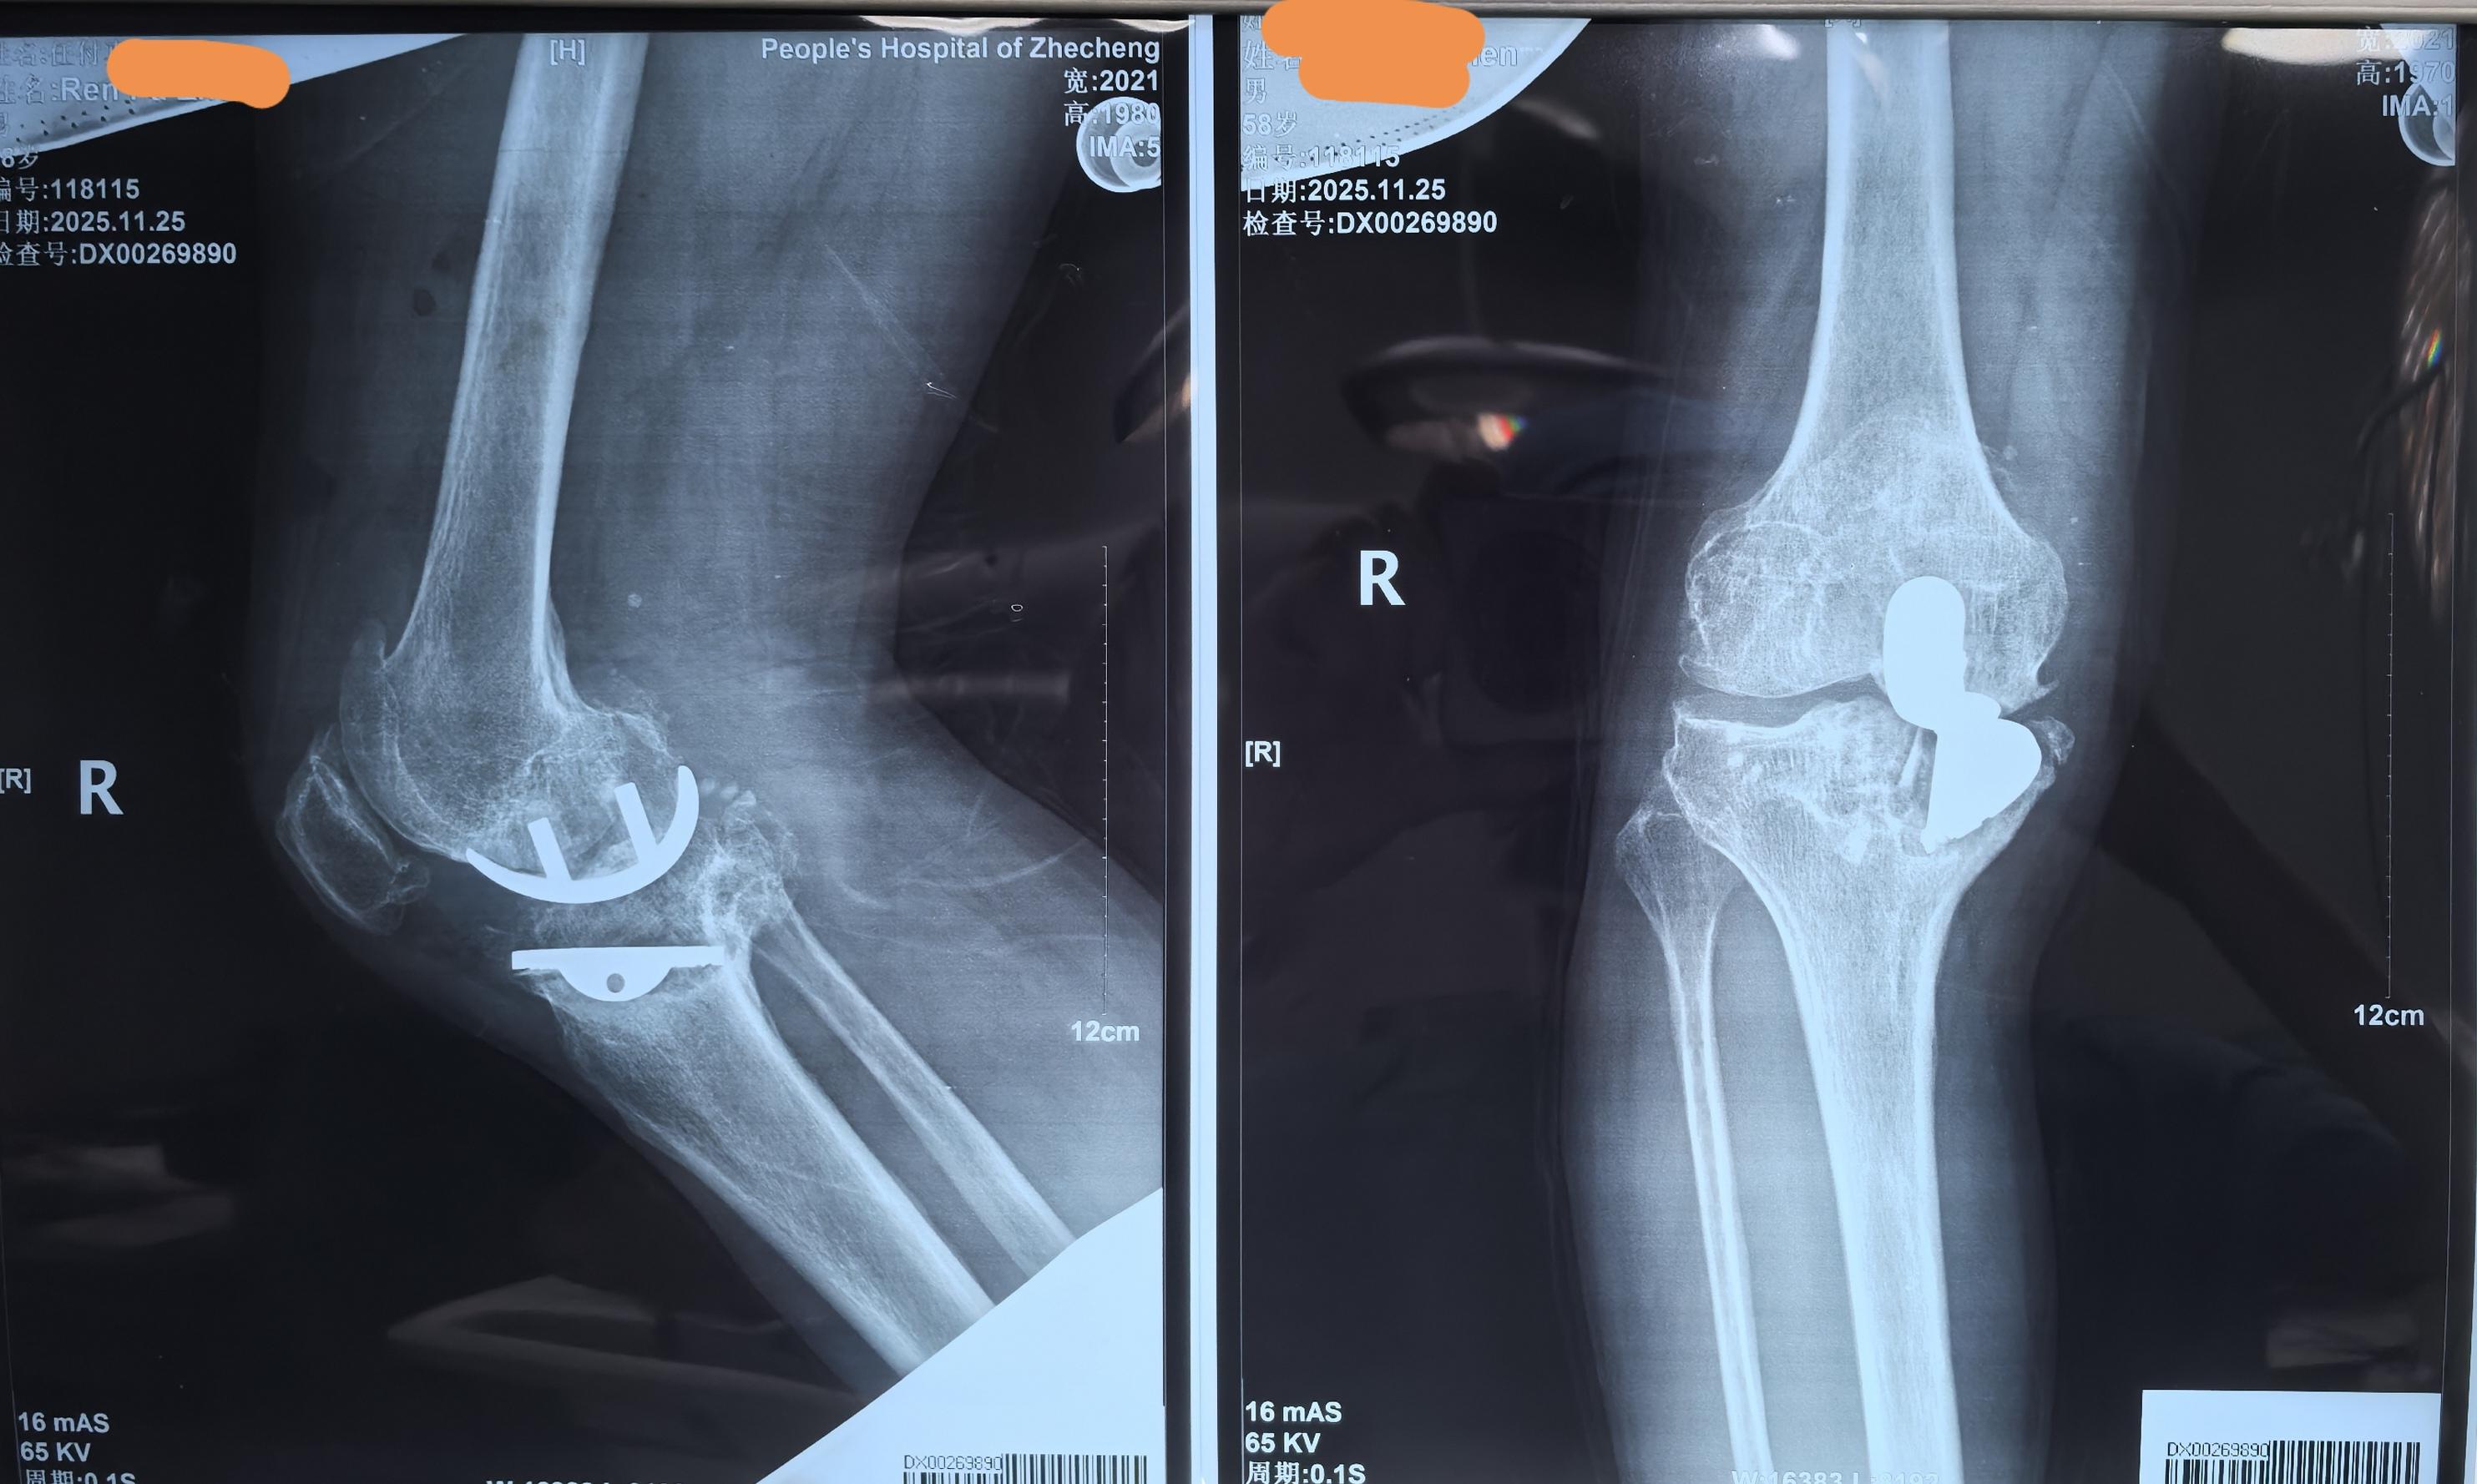

单髁置换术后全膝翻修。单髁置换术后假体松动,双侧全膝翻修。还是那句话,UKA一定严格把握适应症,掌握手术技术要点,才能用的长久。